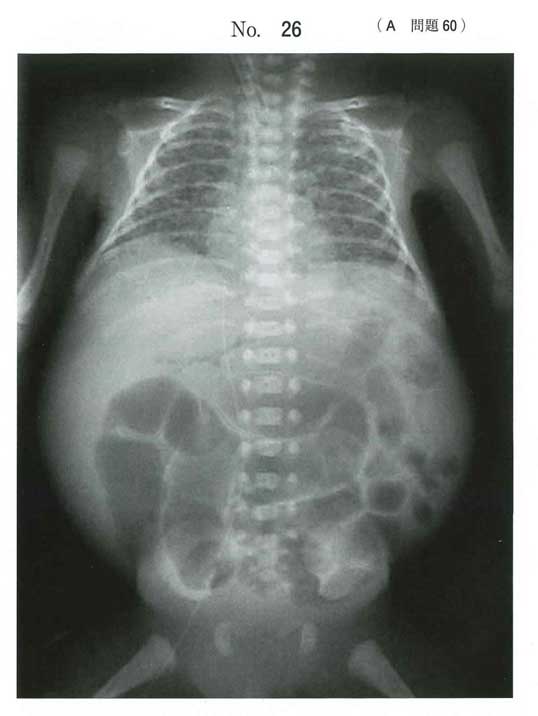

レントゲンが腸管ガスの拡張に加えて腸管壁内ガス(pneumatosis intestinalis:泡状/線状の透亮像) を疑う所見

在胎26週とかなりの早産+人工乳はリスク大